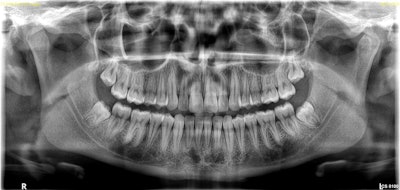

Solution: Minor changes, such as using a different bite block, can often compensate for mispositioning. For example, a Frankfurt block tips the patient's chin down into the ideal position for 3D imaging. For 2D imaging, a new software enhancement called Tomosharp (which you can see an example of below) compensates for less-than-ideal patient positioning by capturing multiple planes in a single acquisition and then analyzing the sharpness of thousands of areas within those slices for a sharper image reconstructed on a 2D plane. Tomosharp is now available with the CS 8100 Evo Edition and CS 8100 3D Evo Edition.